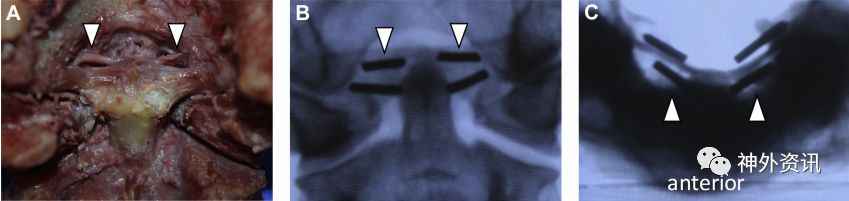

翼状韧带上缘位于齿状突顶部上方或同一水平,其中发现1例标本有枕横韧带,与齿状突顶部无关联。另1标本有副翼状韧带,起自翼状韧带后方,附着于枕髁后部内侧,翼状韧带位于枕髁上(图4)。

图4. 副翼状韧带。A.后面观;B.副翼状韧带和翼状韧带后前位片(正位片);C.副翼状韧带和翼状韧带轴位片。